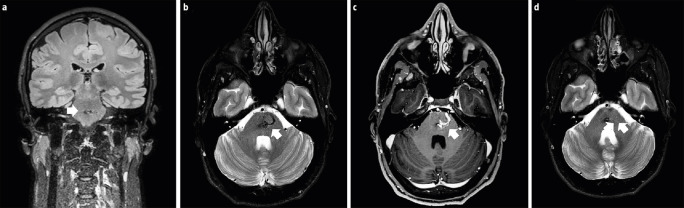

Cefalea crónica diaria refractaria secundaria a malformación arteriovenosa protuberancial medial.

继发于内侧原动静脉畸形的难治性每日慢性头痛。